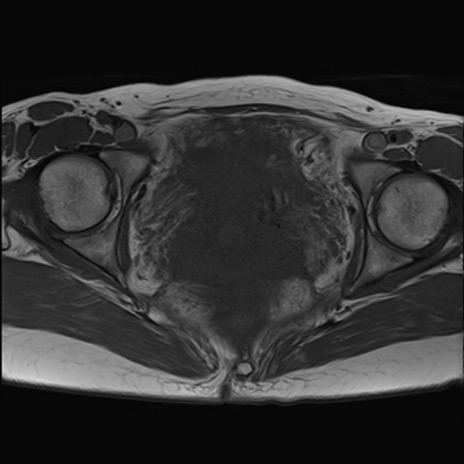

症例39 T1WI(横断像)

【症例】40歳代女性

【主訴】上下腹部痛

【現病歴】2日目から下腹部痛あり。夜間は痛みで眠れなかった。昨日より上腹部痛と下痢が出現。臥位で痛みは軽快したため、休んでいた。本日になって臥位でも立位でも痛みが強くなってきたため救急要請。

【既往歴】子宮内膜症

【身体所見】部:平坦・軟、左上下腹部に圧痛あり、反跳痛あり。

【データ】WBC 21800、CRP 26.78

MRI(4日後)